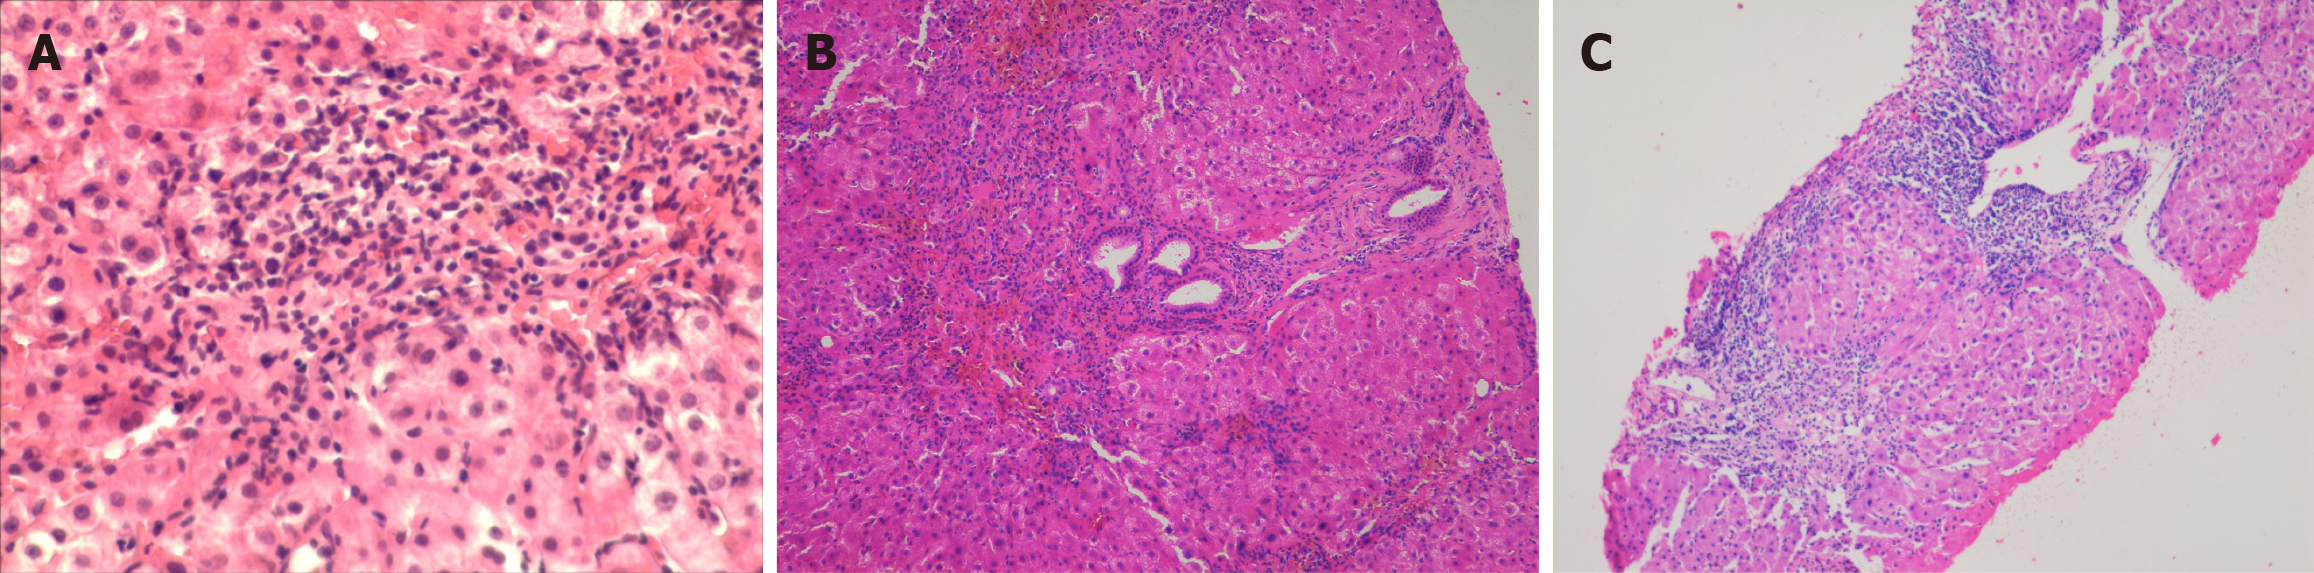

Figure 1 Drug-induced autoimmune-like hepatitis cases from cyproterone acetate, nitrofurantoin, levofloxacin.

A: A 55-year-old male developed drug-induced autoimmune-like hepatitis (DI-ALH) following treatment with cyproterone acetate. Liver histology demonstrated intense lymphoplasmacytic inflammatory infiltrates and marked interface hepatitis. The patient was treated with corticosteroids for one year, achieving sustained biochemical remission. No relapse was observed during a two-year follow-up period after therapy discontinuation of therapy; B: A 70-year-old female developed DI-ALH following two years of nitrofurantoin therapy. Liver histology showed intense lymphoplasmacytic inflammatory infiltrates, bridging fibrosis, and early parenchymal nodularity. The patient was treated with corticosteroids for six months, achieving sustained biochemical remission. No relapse occurred during a three-year follow-up period after therapy discontinuation; C: A 68-year-old male developed DI-ALH following treatment with levofloxacin. Histological examination of the liver revealed findings consistent with active liver cirrhosis, characterized by intense lymphoplasmacytic inflammatory infiltrates and interface hepatitis. The patient was treated with a combination of corticosteroids and azathioprine for one year, resulting in sustained biochemical remission. No relapse was observed during a four-year follow-up period after therapy discontinuation.